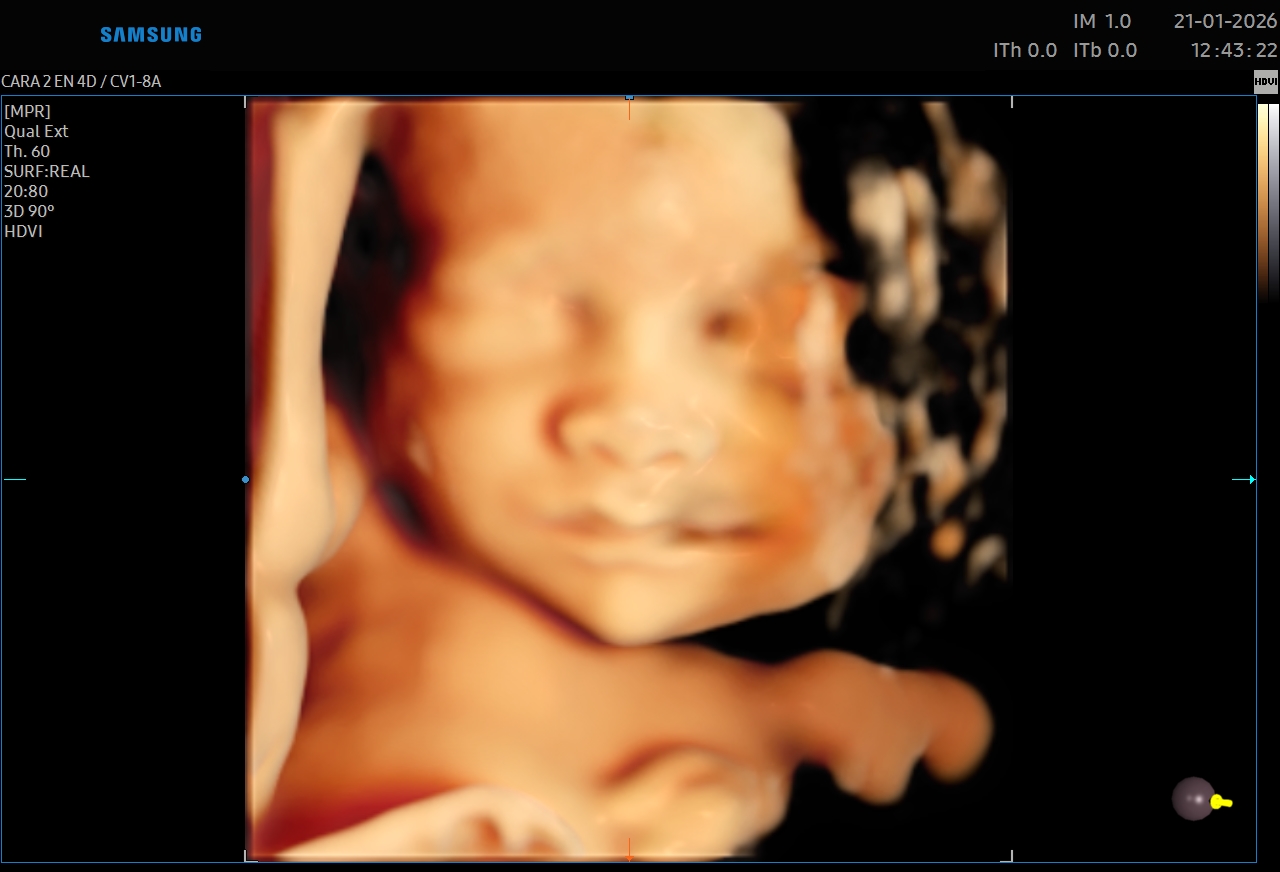

Ecografías 5D